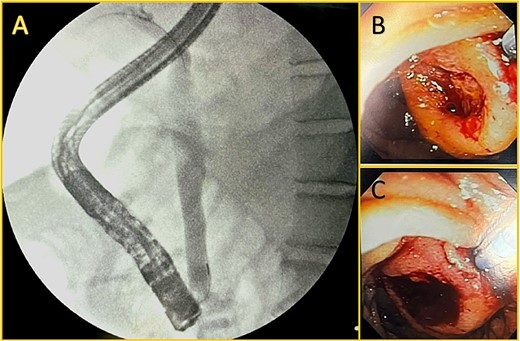

Local complications were suspected, and a contrast-enhanced abdominal computed tomography (CT) was done. It revealed a peripancreatic and perihepatic fluid. The pancreas was enlarged and had several areas of necrosis with gas bubbles (Fig. 1).

Contrast-enhanced computed tomography. A: Perihepatic fluid. B: The pancreatic head, body, and tail have non-enhancing areas compatible with necrosis. C: Dilated biliary duct (leftmost arrow) and Wirsung (rightmost arrow). D: Peripancreatic fluid.